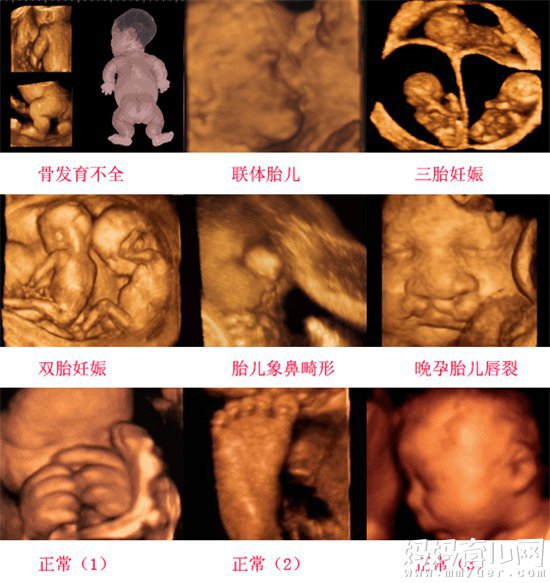

三维彩超表面成像用于产科检查,不仅可观察到胎儿成长的过程,而且可以检查胎盘、羊水及脐带的变化,更重要的是可作为诊断胎儿畸形的主要手段。由于组织结构与液体灰阶反差较大,可清晰显示可疑结构的立体形态、表面特征、空间位置关系,提供胎儿在宫内的立体图像。三维重建包括表面成像、透明成像及多平面成像模式。

过去的B超设备只能检查胎儿的生理指标,而四维彩超还能对胎儿的体表进行检查,如唇裂,脊柱裂,大脑、肾、心脏、骨骼发育不良等,以便尽早的进行治疗。生个聪明健康的小宝宝,并且将宝宝的样子和动作制作成照片或DVD,让宝宝拥有最完整的0岁相册,这已经不再是幻想。

4.过去使用的B超设备只能检查胎儿的一些生理指标,而四维彩超还能对胎儿的体表进行检查,如唇裂,脊柱裂,大脑、肾、心脏、骨骼发育不良等情况,以便尽早的进行治疗。

7.四维彩超能够多方位、多角度地观察宫内胎儿的生长发育情况,为早期诊断胎儿先天性体表畸形和先天性心脏疾病提供准确的科学依据。